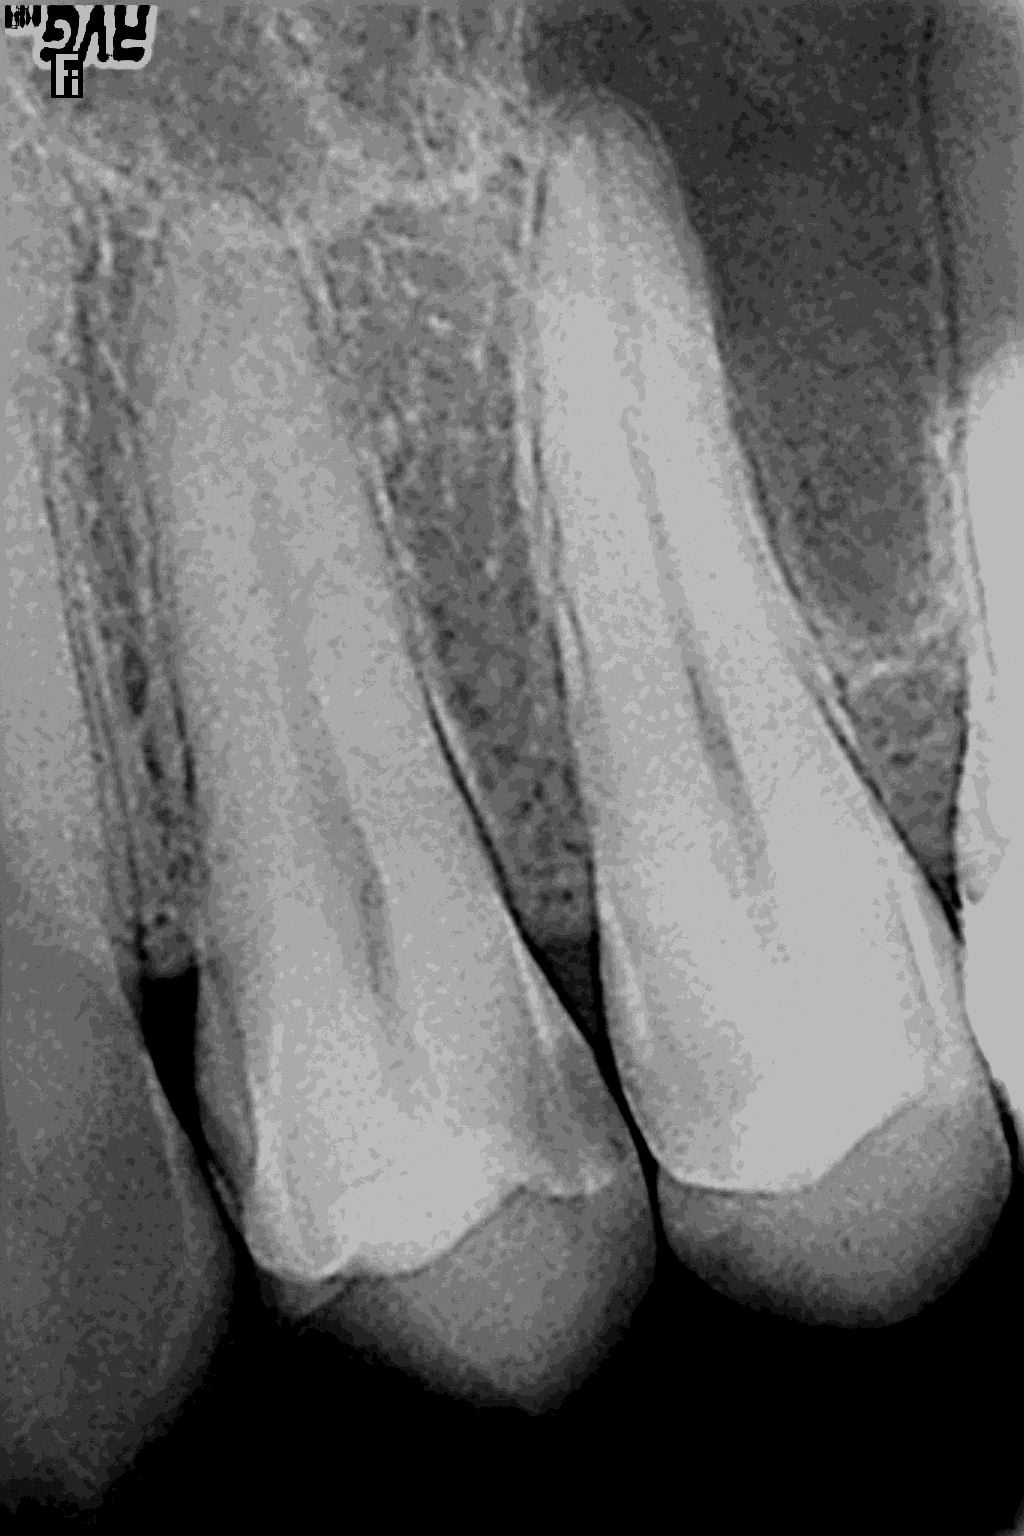

Прицельный снимок. Данный метод диагностики служит для оценки состояния тканей самого зуба, окружающих десен, костной ткани и пародонта десны. Возможности в точной постановке диагноза позволяют использовать этот диагностический метод для выявления очагов воспаления за верхушкой зуба, патологий коронковой части зуба, контроля качества пломбирования зубов.

Рентген зубов. Рентгеновское обследование зуба является важнейшим этапом комплексного лечения различных стоматологических заболеваний. Рентгеновский снимок предоставляет важную информацию о состоянии зубов, корней, наличии кариеса, кист, опухолей и т.д.